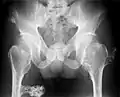

múltiples osteocondromas en la pelvis

Un bulto notable en relación con una extremidad puede ser el primer síntoma de presentación. Pueden surgir múltiples deformidades, a saber, deformidades del plano coronal alrededor de las rodillas, tobillos, hombros, codos y muñecas. Por ejemplo, se encuentran genu valgum (golpe de rodillas), tobillo valgo, arqueamiento y acortamiento cubital y subluxación de la cabeza radial. La mayoría de las personas afectadas tienen osteocondromas clínicamente manifestados alrededor de la rodilla. La participación del antebrazo en HMO es considerable.[1][4] Además, puede ocurrir baja estatura y generalmente es desproporcionada. Estas manifestaciones suelen ser el resultado de la interrupción del crecimiento de la fisis, especialmente porque los osteocondromas normalmente surgen en los extremos metafisarios de los huesos largos en las proximidades de la fisis. Los osteocondromas intraarticulares de la cadera pueden inducir limitación del rango de movimiento, dolor articular y displasia acetabular.[2] Asimismo, puede producirse dolor articular en otras localizaciones y compresión neurovascular. Además, la discapacidad funcional con respecto a las actividades de la vida diaria puede ser una característica de presentación. El dolor de la deformidad espinal o el compromiso neurológico deben despertar sospechas de afectación de las vértebras.[3]